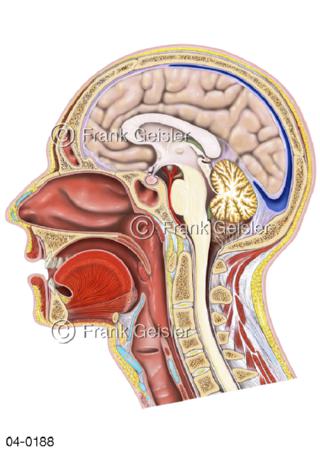

Bildergalerie Topografie Organe

Bilder zur topografischen Anatomie, die Lage der Organe und die Strukturen nach ihren räumlichen Lagebeziehungen zueinander, Übersicht der inneren Organe im Kopf und im Rumpf, Topografie der Organe im Brustraum (Thorax) und im Bauchraum (Abdomen)